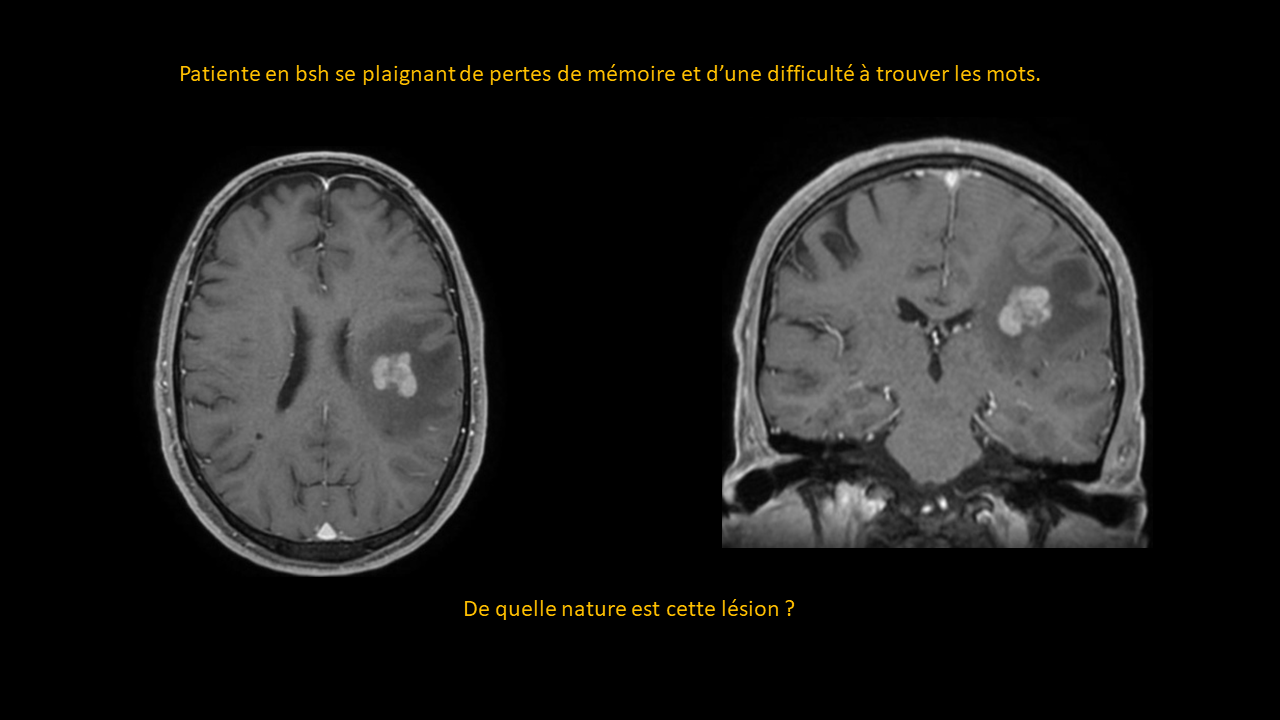

Formation continue sous forme de vignettes ( Quiz )